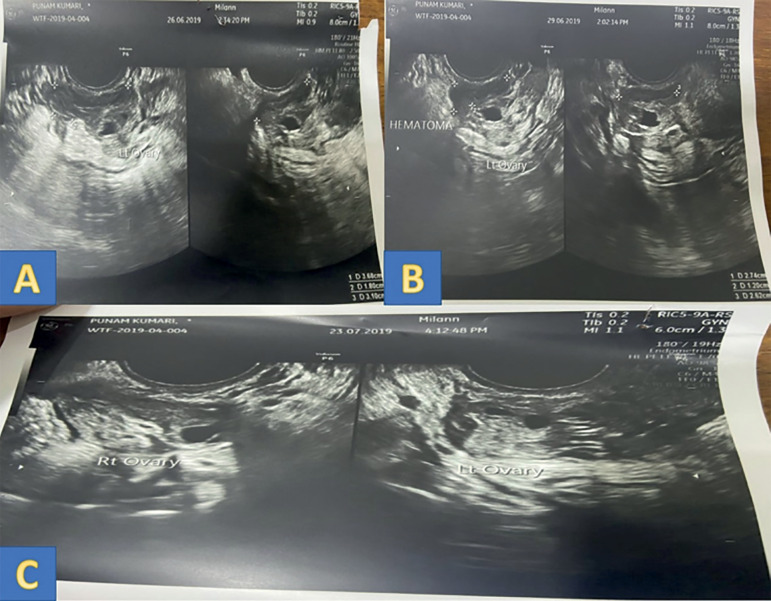

Management of peri-ovarian hematoma following oocyte retrieval in a pooling cycle IVF: Case report.

Here we report a case of peri-ovarian hematoma following ovum pick-up in a patient in a pooling cycle IVF (in vitro fertilization). We have attempted to discuss the possible mechanisms for the development of hematoma in such patients, the common clinical presentation, monitoring, and management of these cases. The decision to operate or to manage conservatively forms an important aspect of managing such patients. This case report can help to keep the clinicians alert while managing this subgroup of patients.